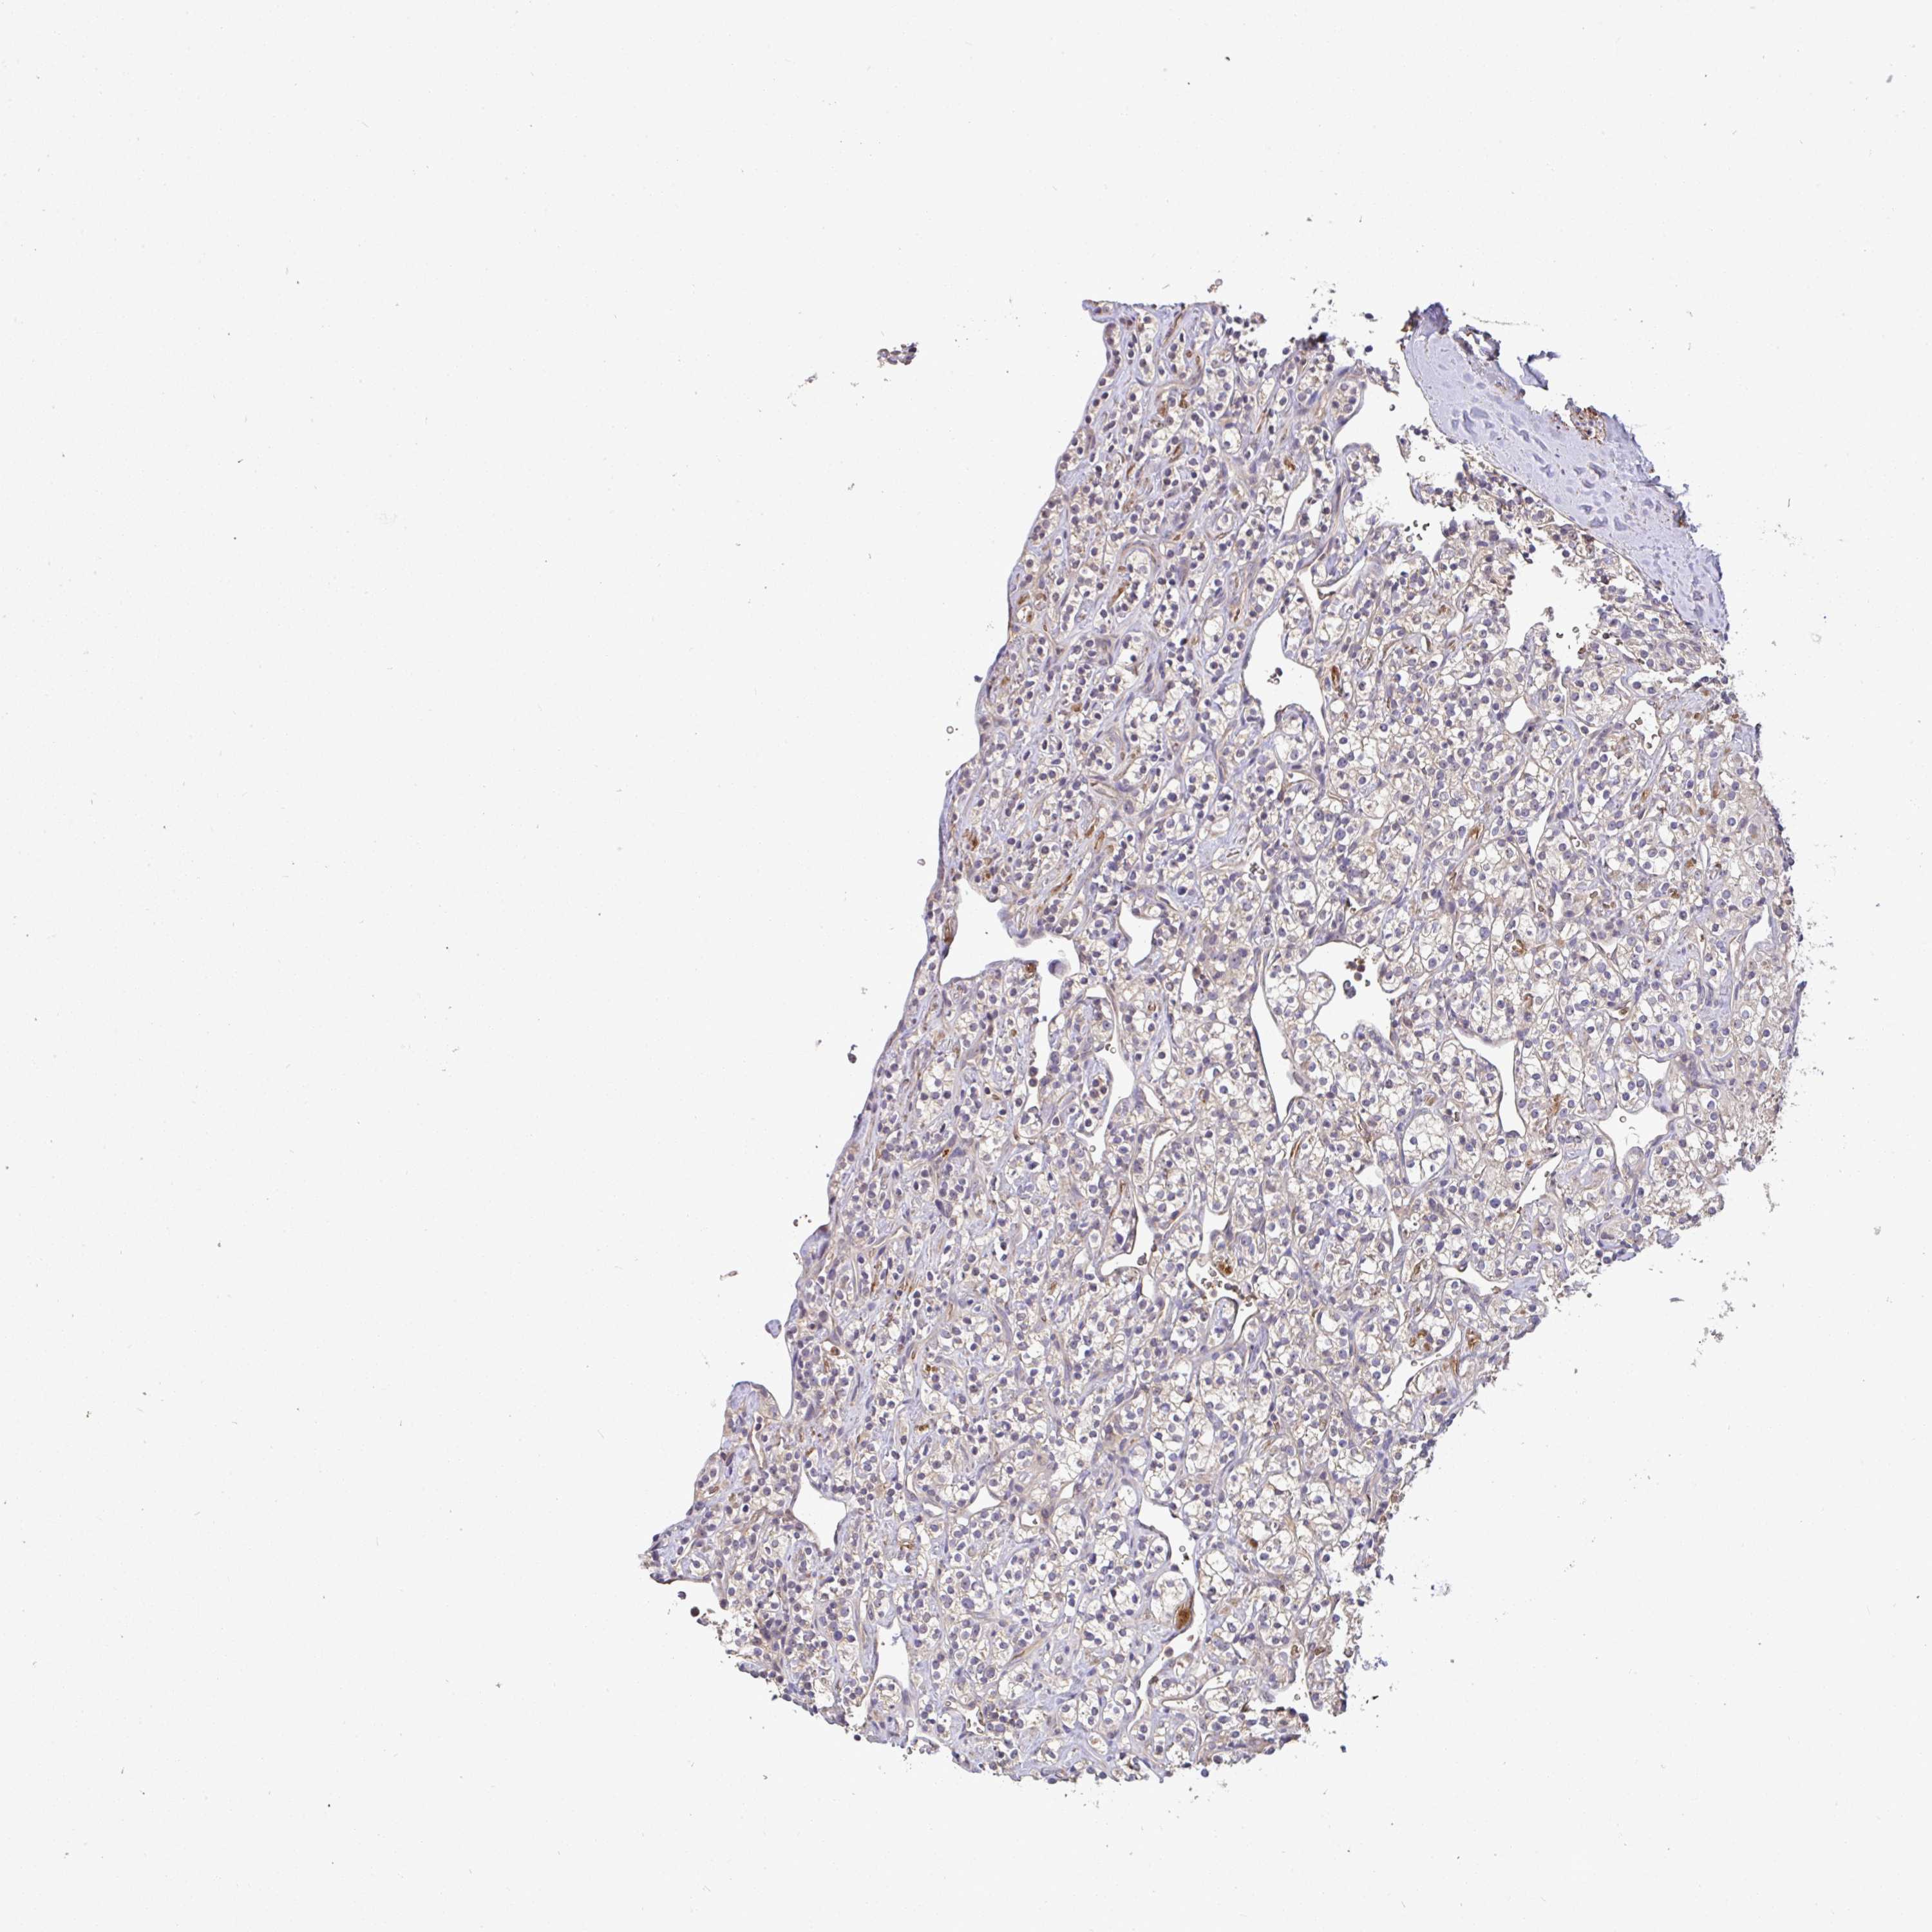

KIDNEY RENAL PAPILLARY CELL CARCINOMA (TCGA) - Interactive survival scatter ploti

The Survival Scatter plot shows the clinical status (i.e. dead or alive) for all individuals in the patient cohort, based on the same data that underlies the corresponding Kaplan-Meier plots. Patients that are alive at last time for follow-up are shown in blue and patients who have died during the study are shown in red.

The x-axis shows the expression levels (FPKM) of the investigated gene in the tumor tissue at the time of diagnosis. The y-axis shows the follow-up time after diagnosis (years). Both axes are complimented with kernel density curves demonstrating the data density over the axes. The top density plot shows the expression levels (FPKM) distribution among dead (red) and alive patients (blue). The right density plot shows the data density of the survived years of dead patients with high and low expression levels respectively, stratified using the cutoff indicated by the vertical dashed line through the Survival Scatter plot. This cutoff is automatically defined based on the FPKM cutoff that minimizes the p-score. The cutoff can be changed by dragging the vertical line or by entering a cutoff value in the square labeled "Current cut-off".

Under the Survival Scatter plot the p-score landscape (black curve; left axis) is shown together with dead median separation (red curve; right axis). Dead median separation is the difference in median mRNA expression between patients who have died with high and low expression, respectively. It is calculated as follows: median FPKM expression of dead patients with high expression - median FPKM expression of dead patients with low expression. This is intended to aid the user in visually exploring custom cutoffs and the associated p-scores and dead median separation.

Individual patient data is displayed and can be filtered by clicking on one or more of the category buttons on the top of the page. Categories describing expression level and patient information include: high, low, alive, dead, female, male and tumor stages. The scale of the x-axis can be toggled between linear and log-scale by clicking on the "x log" button. Mouse-over function shows TCGA ID, patient information and mRNA expression (FPKM) for each patient.

& Survival analysisi

Kaplan-Meier plots summarize results from analysis of correlation between mRNA expression level and patient survival. Patients were divided based on level of expression into one of the two groups "low" (under cut off) or "high" (over cut off). X-axis shows time for survival (years) and y-axis shows the probability of survival, where 1.0 corresponds to 100 percent.

C1QTNF9B is not prognostic in Kidney Renal Papillary Cell Carcinoma (TCGA)

: 1.48